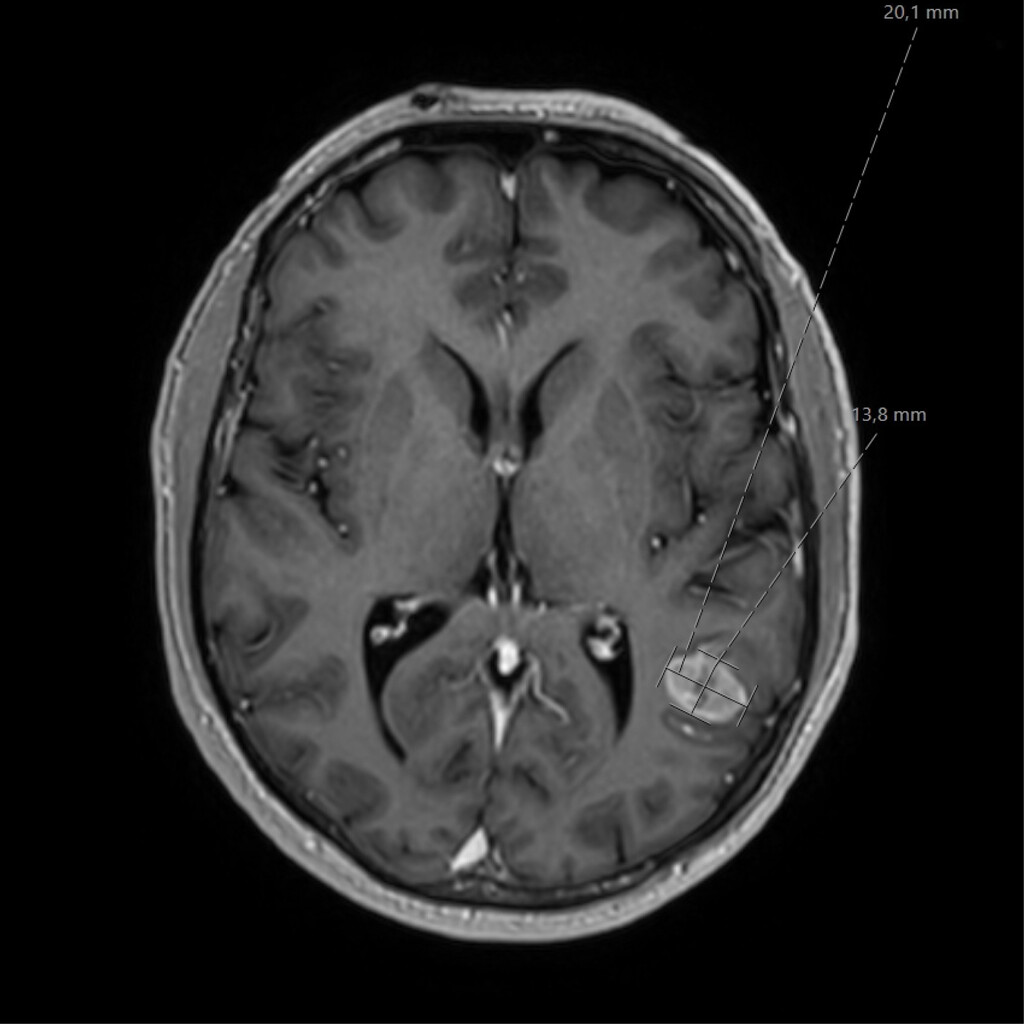

Een 61-jarige man komt op de SEH vanwege acuut ontstane onsamenhangende spraak. Hij spreekt wel vloeiend en zijn begrip is intact (audiofragment). Een CT-scan van de hersenen laat een afwijking met contrastaankleuring zien ter hoogte van het spraakcentrum. Na een eenmalige gift midazolam en intraveneuze behandeling met levetiracetam normaliseert de spraak.